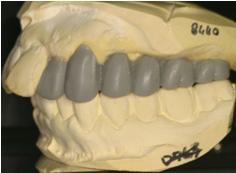

歯周病・根の治療・抜歯・虫歯の治療をおこない、仮歯で咬めるようにしました。

![]() |

左上・右下奥歯はインプラント治療を希望され診断用ワックスアップを製作しました。 |